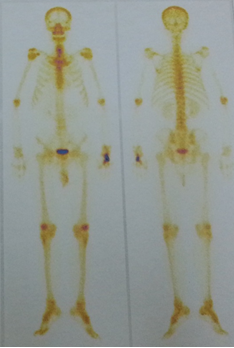

-   Cắt lớp vi tính lồng ngực: U thùy dưới phổi phải kích thước 56x81mm, ngấm thuốc sau tiêm. Khối mờ đỉnh phổi trái kích thước 28mm, nốt mờ nhỏ phân thùy lưỡi phổi trái.

Hình 1: Hình ảnh chụp cắt lớp vi tình lồng ngực

-   Chụp cắt lớp vi tính lồng ngực:

Trước điều trị: U phổi phải kích thước 56x81mm

Sau điều trị: U phổi phải kích thước 35x40mm

Trước điều trị: Khối mờ đỉnh phổi trái kích thước 28mm, nốt mờ thùy dưới phổi trái.

Sau điều trị: Khối mờ đỉnh phổi trái là dải xơ hóa, nốt mờ nhỏ thùy dưới phổi trái không còn.